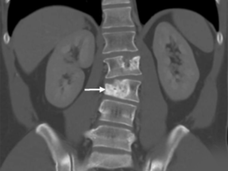

SBRT Emerging as an Important Treatment for Early-Stage Kidney Cancer

Stereotactic body radiotherapy was effective in people with localized kidney cancer who weren’t able to have surgery to remove their tumor, a clinical trial has shown. No patients had their cancer start growing or died from cancer over the next 5 years.